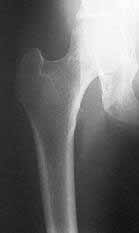

La enfermedad de Paget se maneja con calcitonina, y la osteoporosis, con medidas preventivas, ejercicio, dieta, suplencia de calcio y vitamina D, terapia hormonal de suplencia y bisfosfonatos

(Figura 4. La radiografía muestra cuello de fémur osteoporótico).